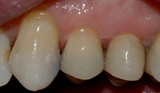

![]()

Bildet viser at en tyggeknute til en tann i overkjeven har frakturert. Tannen var svekket på grunn av en stor amalgamfylling.